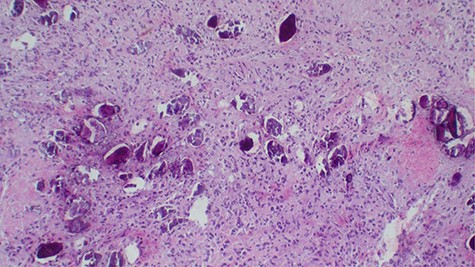

Laboratory investigations revealed a low platelet level of 53 per microliter and hemoglobin level of 10.7 g/dl. Renal profile, white blood count and serum electrolytes were within normal range. Computed tomography intravenous urogram revealed a large heterogeneous mass, measuring 5.5 × 4.5 cm at the right superolateral aspect of the urinary bladder with ipsilateral hydronephrosis and hydroureter. Bone scan study was unremarkable. Urothelial cell carcinoma of the urinary bladder was clinically suggested as the most likely differential diagnosis. Cystoscopy was done under spinal anesthesia, which revealed a solid mass with areas of necrosis at the anterior bladder wall. The biopsy was taken whose histological evaluation revealed a high-grade malignant mesenchymal tumor made up of oval or spindle cells with osteoid formation in many areas of the lesion (Fig. 1). No definite carcinomatous component was appreciated. The tumor was strongly positive for vimentin immunohistochemistry staining (Fig. 2) and negative for cytokeratin 20. Calcified schistosomal ova were also seen (Fig. 3).

Histopathology of urinary bladder tumor showing oval- to spindle-shaped cells with abundant osteoid matrix deposition (H&E stain, ×200).